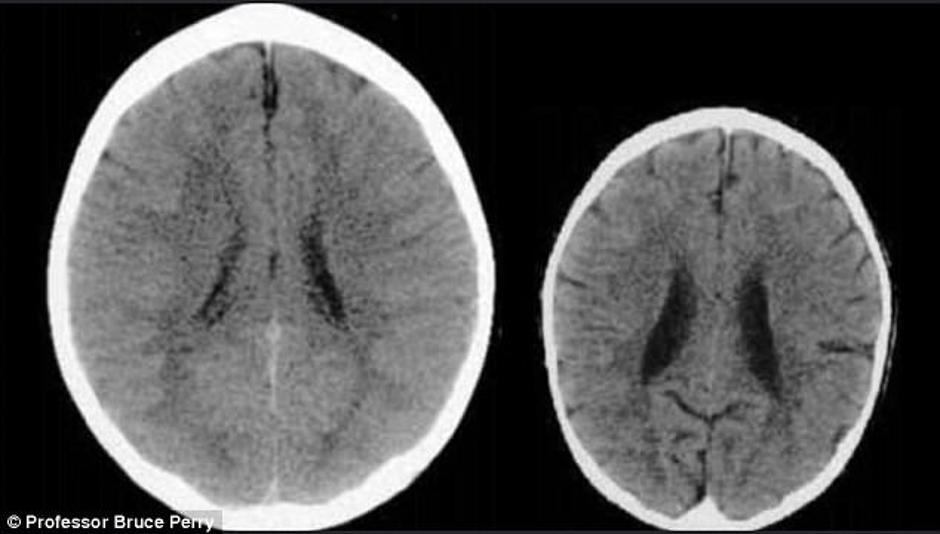

Snimke mozgova dvaju djeteta pokazala su šokantne razlike. Podijelio ih je Bruce Perry, glavni psihijatar u teksaškoj bolnici.

Lijeva snimka pokazuje dijete koje je odraslo u okruženju koje ga je poticalo i ohrabrivalo, dok je desna snimka ona djeteta koje je bilo zanemarivano.

Ne samo da je mozak zlostavljanog djeteta manji, već su njegovi dijelovi na CT snimci puno mutniji.

- Ove snimke ilustriraju negativan utjecaj zanemarivanja na mozak u razvoju - zaključuje Perry.